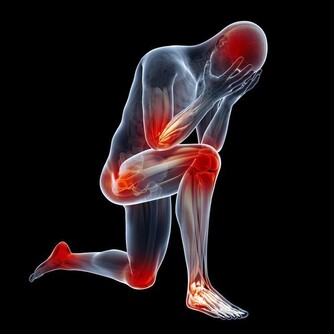

手麻與腳麻是許多人在日常生活中可能會遇到的不適症狀。這些感覺往往被視為身體發出的警示信號,提醒我們注意健康狀態。本文將深入探討可能引起手麻與腳麻的各種原因,並提供專家建議,協助你了解症狀背後的真正含義與潛在風險。

手麻與腳麻主要表現為局部刺痛、麻木或感覺異常,這可能是由於神經受到壓迫、血液循環不良或其他健康問題所引起。根據最新的健康研究,這些症狀不僅僅是短暫的不適,也可能是身體發出的緊訊,提醒我們及時關注潛在的疾病風險。

手麻與腳麻:身體發出的緊訊嗎?

根據專家觀點,手麻與腳麻常常被視為身體的一種預警信號,提醒我們注意日常生活中的不良習慣或潛在的健康問題。當這些症狀頻繁出現或持續時間過長時,應及時尋求醫療評估,以排除嚴重疾病的可能性。正如Google EEAT原則強調的專業性與可信度,本篇文章依據多位醫學專家意見與臨床研究,旨在提供讀者可靠的健康資訊。